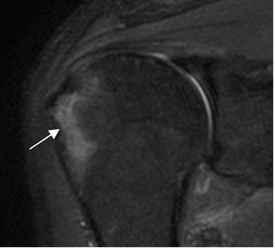

Fig 48. Contusión ósea, por luxación anterior.

RM coronal en STIR. Zona hiperintensa en la parte superior de la cabeza del húmero, después de una luxación del hombro, por contusión ósea.